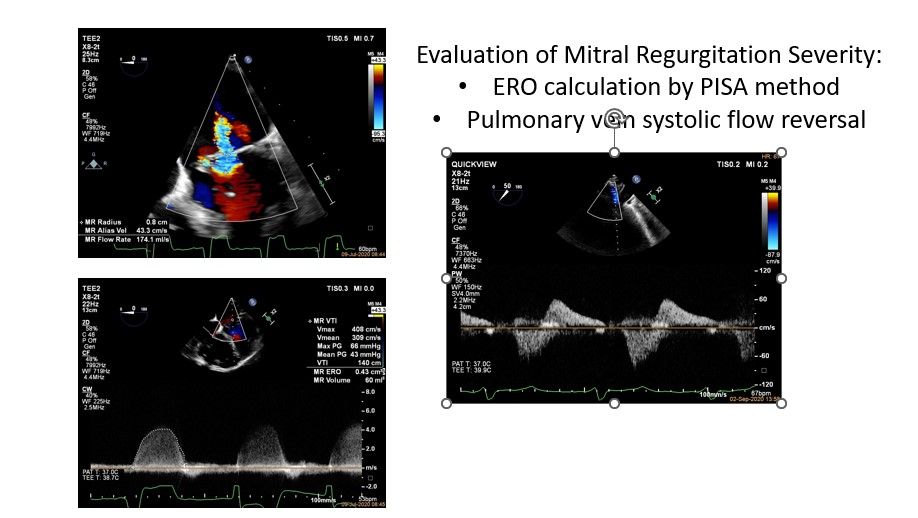

• Severe mitral regurgitation (ERO 43mm 2 , R VOL 60ml)

Significant mitral regurgitation due to annular dilatation and hypermobility of both leaflets with some degenerative changes ERO 43mm 2 R VOL 60ml